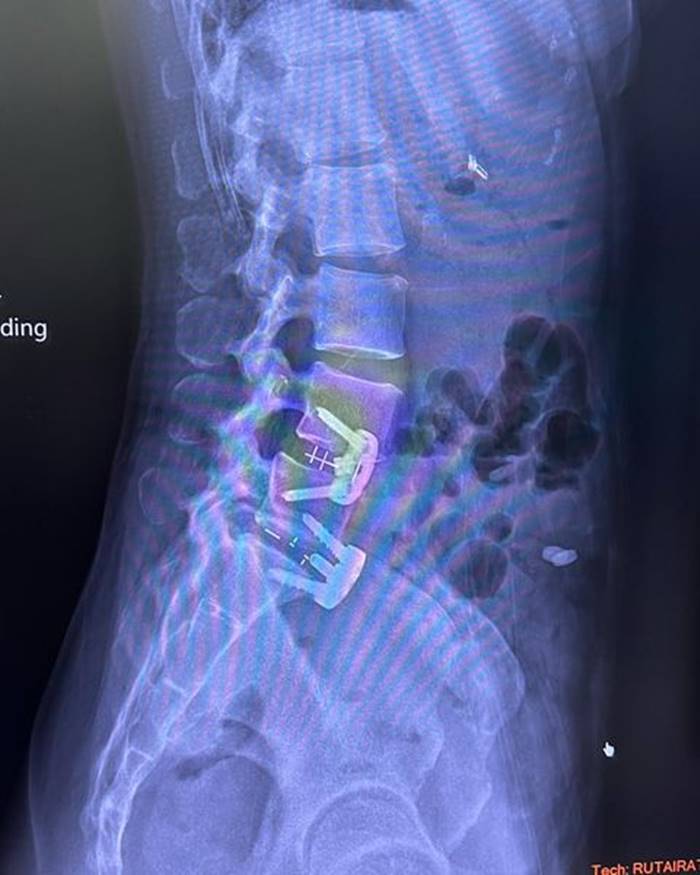

อยากขอเตือนเพื่อนๆ นะคะ ว่าถ้าออกกำลังท่าไหนแล้วรู้ตัวว่าไม่ไหวก็ให้บอก trainer ค่ะ อย่าฝืนทำ เพราะลงท้ายอาจจะต้องผ่าตัดแบบหนุ่ย.. trainer ให้ทำ Squat ที่หนุ่ยก็หันไปบอกแล้วว่าหนักไปทำไม่ได้ เค้าก็ยังให้ทำ ผลคือหมอนรองกระดูกปลิ้น ต้องผ่าตัดใส่เหล็กตามภาพเลยค่ะ..ตอนนี้ก็ต้อง slowlife ไป 4-5 เดือน”